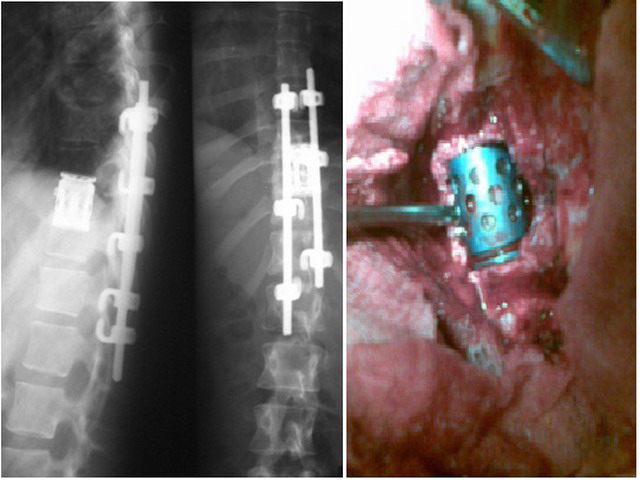

При злокачественных и метастатических поражениях позвонков выполняются различные операции по декомпрессии нервных структур и фиксации позвоночника. Они направлены в первую очередь на устранение боли, восстановление опорности, стабилизацию позвоночника и улучшение качества жизни. Что позволяет пациентам сохранить способность передвигаться и уменьшить их страдания. При единичных метастазах возможны и радикальные операции с протезированием позвонков.